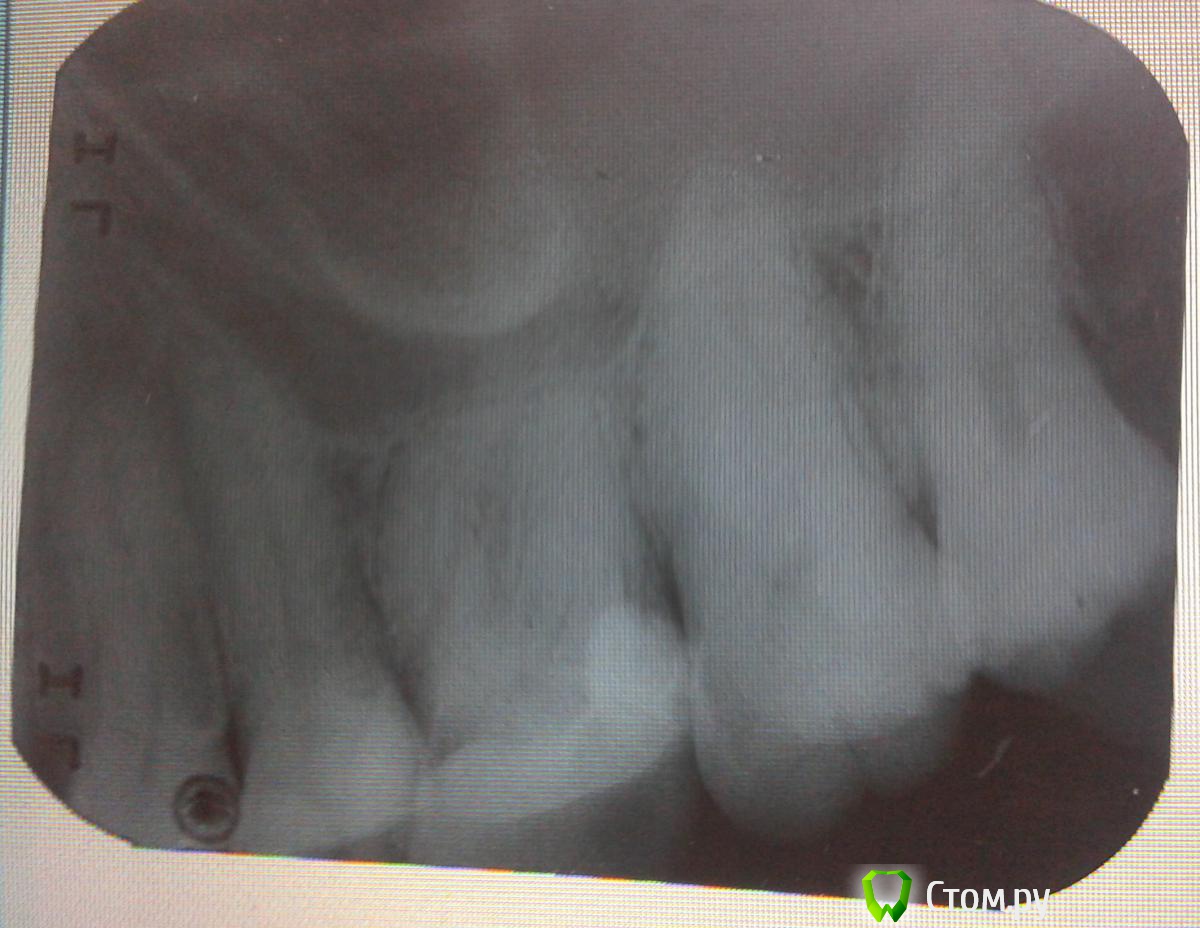

jannaa Опубликовано 19 февраля, 2014 Поделиться Опубликовано 19 февраля, 2014 Здравствуйте , дорогие врачи , помогите, пожалуйста с диагнозом ! я сейчас вдали от дома в маленьком городе и болеть очень страшно... Заболело всё в один день - сначала рёбра сзади резко , я решила что это невралгия и выпила побольше бальзама , и в этот же день ела орешек и вдруг - резкая мгновенная боль там попалась скорлупка , но всё быстро прошло и ничего не болело кроме рёбер сзади , на следующий день у меня вскочил герпес , зуб не болел а реагировал на холод , проходило мгновенно при полоскании содой ( этот же зуб реагировал много лет назад подобным образом где то 2 дня) После сауны и басика становилось хуже , я ощущала слабость , через 3 дня герпес почти прошёл, и стала болеть челюсть и голова , иногда кисть руки , голова, особенно челюсть и вокруг глаз и затылок . Зубами жевала всеми .Эта боль была в любое время но ночью всё тихо было , возникала спонтанно - как только я садилась за работу или от холодного чая или вообще еды . Стала лечить невралгию ( ибуклин ( нестероидное противоспалительное), зеребролизад внутримышечно и В1 ,6,12 тоже уколы . Стало намного лучше - я стала соображать , гоова не болит , чувствую себя намного бодрее , но через 3 дня после лечения больно нажимать на зуб , десна вокруг зуба опухла как мне кажется и при пальпации иногда болезненна , плохого запаха нет . Пришлось идти к стоматологу , по снимку ничего не сказала , предложила удалить нервы . А мне очень не хочется их терять , так как с другой стороны одного зуба уже нет ( потеряла когда была глупая ) . Может сделать КТ , или по другому диагноз поставить ? не очень также хочется вскрывать зуб - этот зуб делала мой любимый врач из спб Кукояшная Елена Игоревна в декабре , совсем недавно и всё до этих странных событий было замечательно ... Если вдавить в зуб зубочистку , то сильнее болит когда вдавливаеш , а если отпускаеш , боль плавненько стихает в течении 2 секунд . Эти нерво боли исчезли , тоесть боль теперь просто боль , а не такая что думаеш , что пришёл конец Может мне сделать КТ , если он тут есть ? Завтра схожу к невропатологу на всякий случай . Снимок такой и был - плохого качества и неконтрастный , снимали 2 раза , второй такой же . И не понятно где корень зуба , который как раз и болит при надавливании ... Если у вас есть вопросы по вентиляции или сайтам - пишите ! я инженер и вэбмастер Ссылка на комментарий

jannaa Опубликовано 19 февраля, 2014 Автор Поделиться Опубликовано 19 февраля, 2014 (изменено) А зуб-то который беспокоит?Если припухла десна и больно накусывать,то с большой долей вероятности нерв там уже "умер".http://prntscr.com/2txpbd по моим подсчётам вот этот - который на снимке без корня...а могут нервы умереть из за травмы скорлупой от орехов ? до этого зуб был нориальный , в декабре поставила пломбу , тк старая упала опять же из орешков в конфетах ) Изменено 19 февраля, 2014 пользователем jannaa Ссылка на комментарий